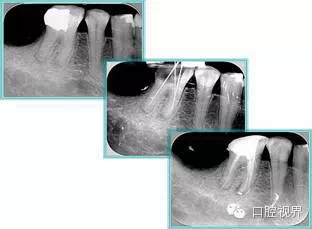

2. X 線片

共有 4 張 X 線片,分別是術(shù)前、診斷絲 、主牙膠尖確認(rèn)、術(shù)后。

( 1 )術(shù)前:術(shù)前 X 線片用來了解牙齒的大概情況。術(shù)前預(yù)期為多根牙時(shí) X 線片應(yīng)偏頭拍攝。

( 2 )診斷絲:根據(jù)術(shù)前 X 線片進(jìn)行開髓、根管的初步預(yù)備后,需要插入診斷絲,用來指示工作器械位置。常用 10 號或 15 號擴(kuò)大器作為診斷絲插入牙髓腔。

( 3 )主牙膠尖確認(rèn):通過術(shù)前預(yù)期和診斷絲診斷,明確工作長度、牙根走向,進(jìn)行根管預(yù)備。之后應(yīng)進(jìn)行主牙膠尖(中銼)確認(rèn),已明確根管是否適合充填。

( 4 )術(shù)后:觀察治療效果。